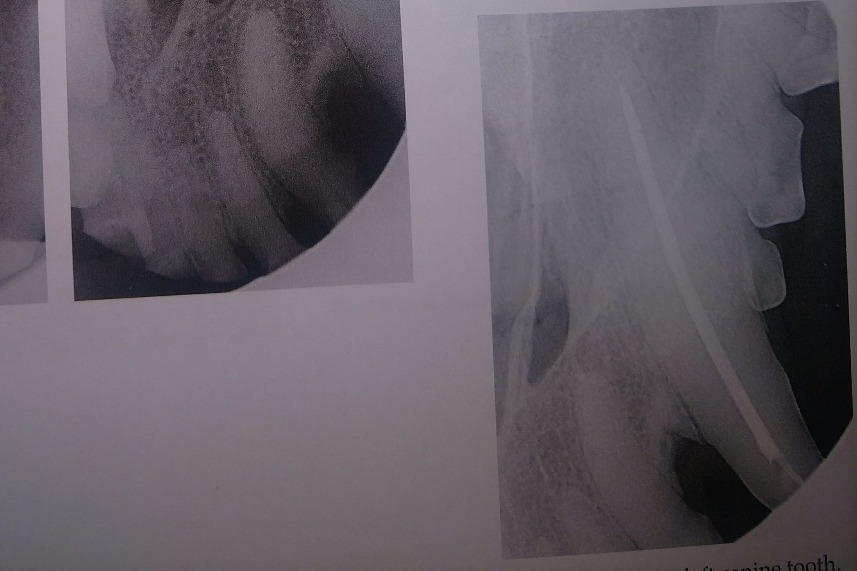

The radiographs laid out a dim story of that long term damage: all 4 canine teeth were dead, 2 of those canines were broken off from the recent attempt on the gate; all of her lower incisors, and several molars on each side were also dead. The vet was surprised, in spite of massively evident wear and tear, that her upper incisors appeared to still be alive. More of her teeth were dead than live. However, there was some good news in that her gums were completely free of gum disease, she had very little plaque and tartar buildup, and that she hadn't lost any of the bone her teeth were seated in.

The following photos are her radiographs for anyone that knows how to read them, so you can see all the dead teeth that need future extractions, and some show the root canals: